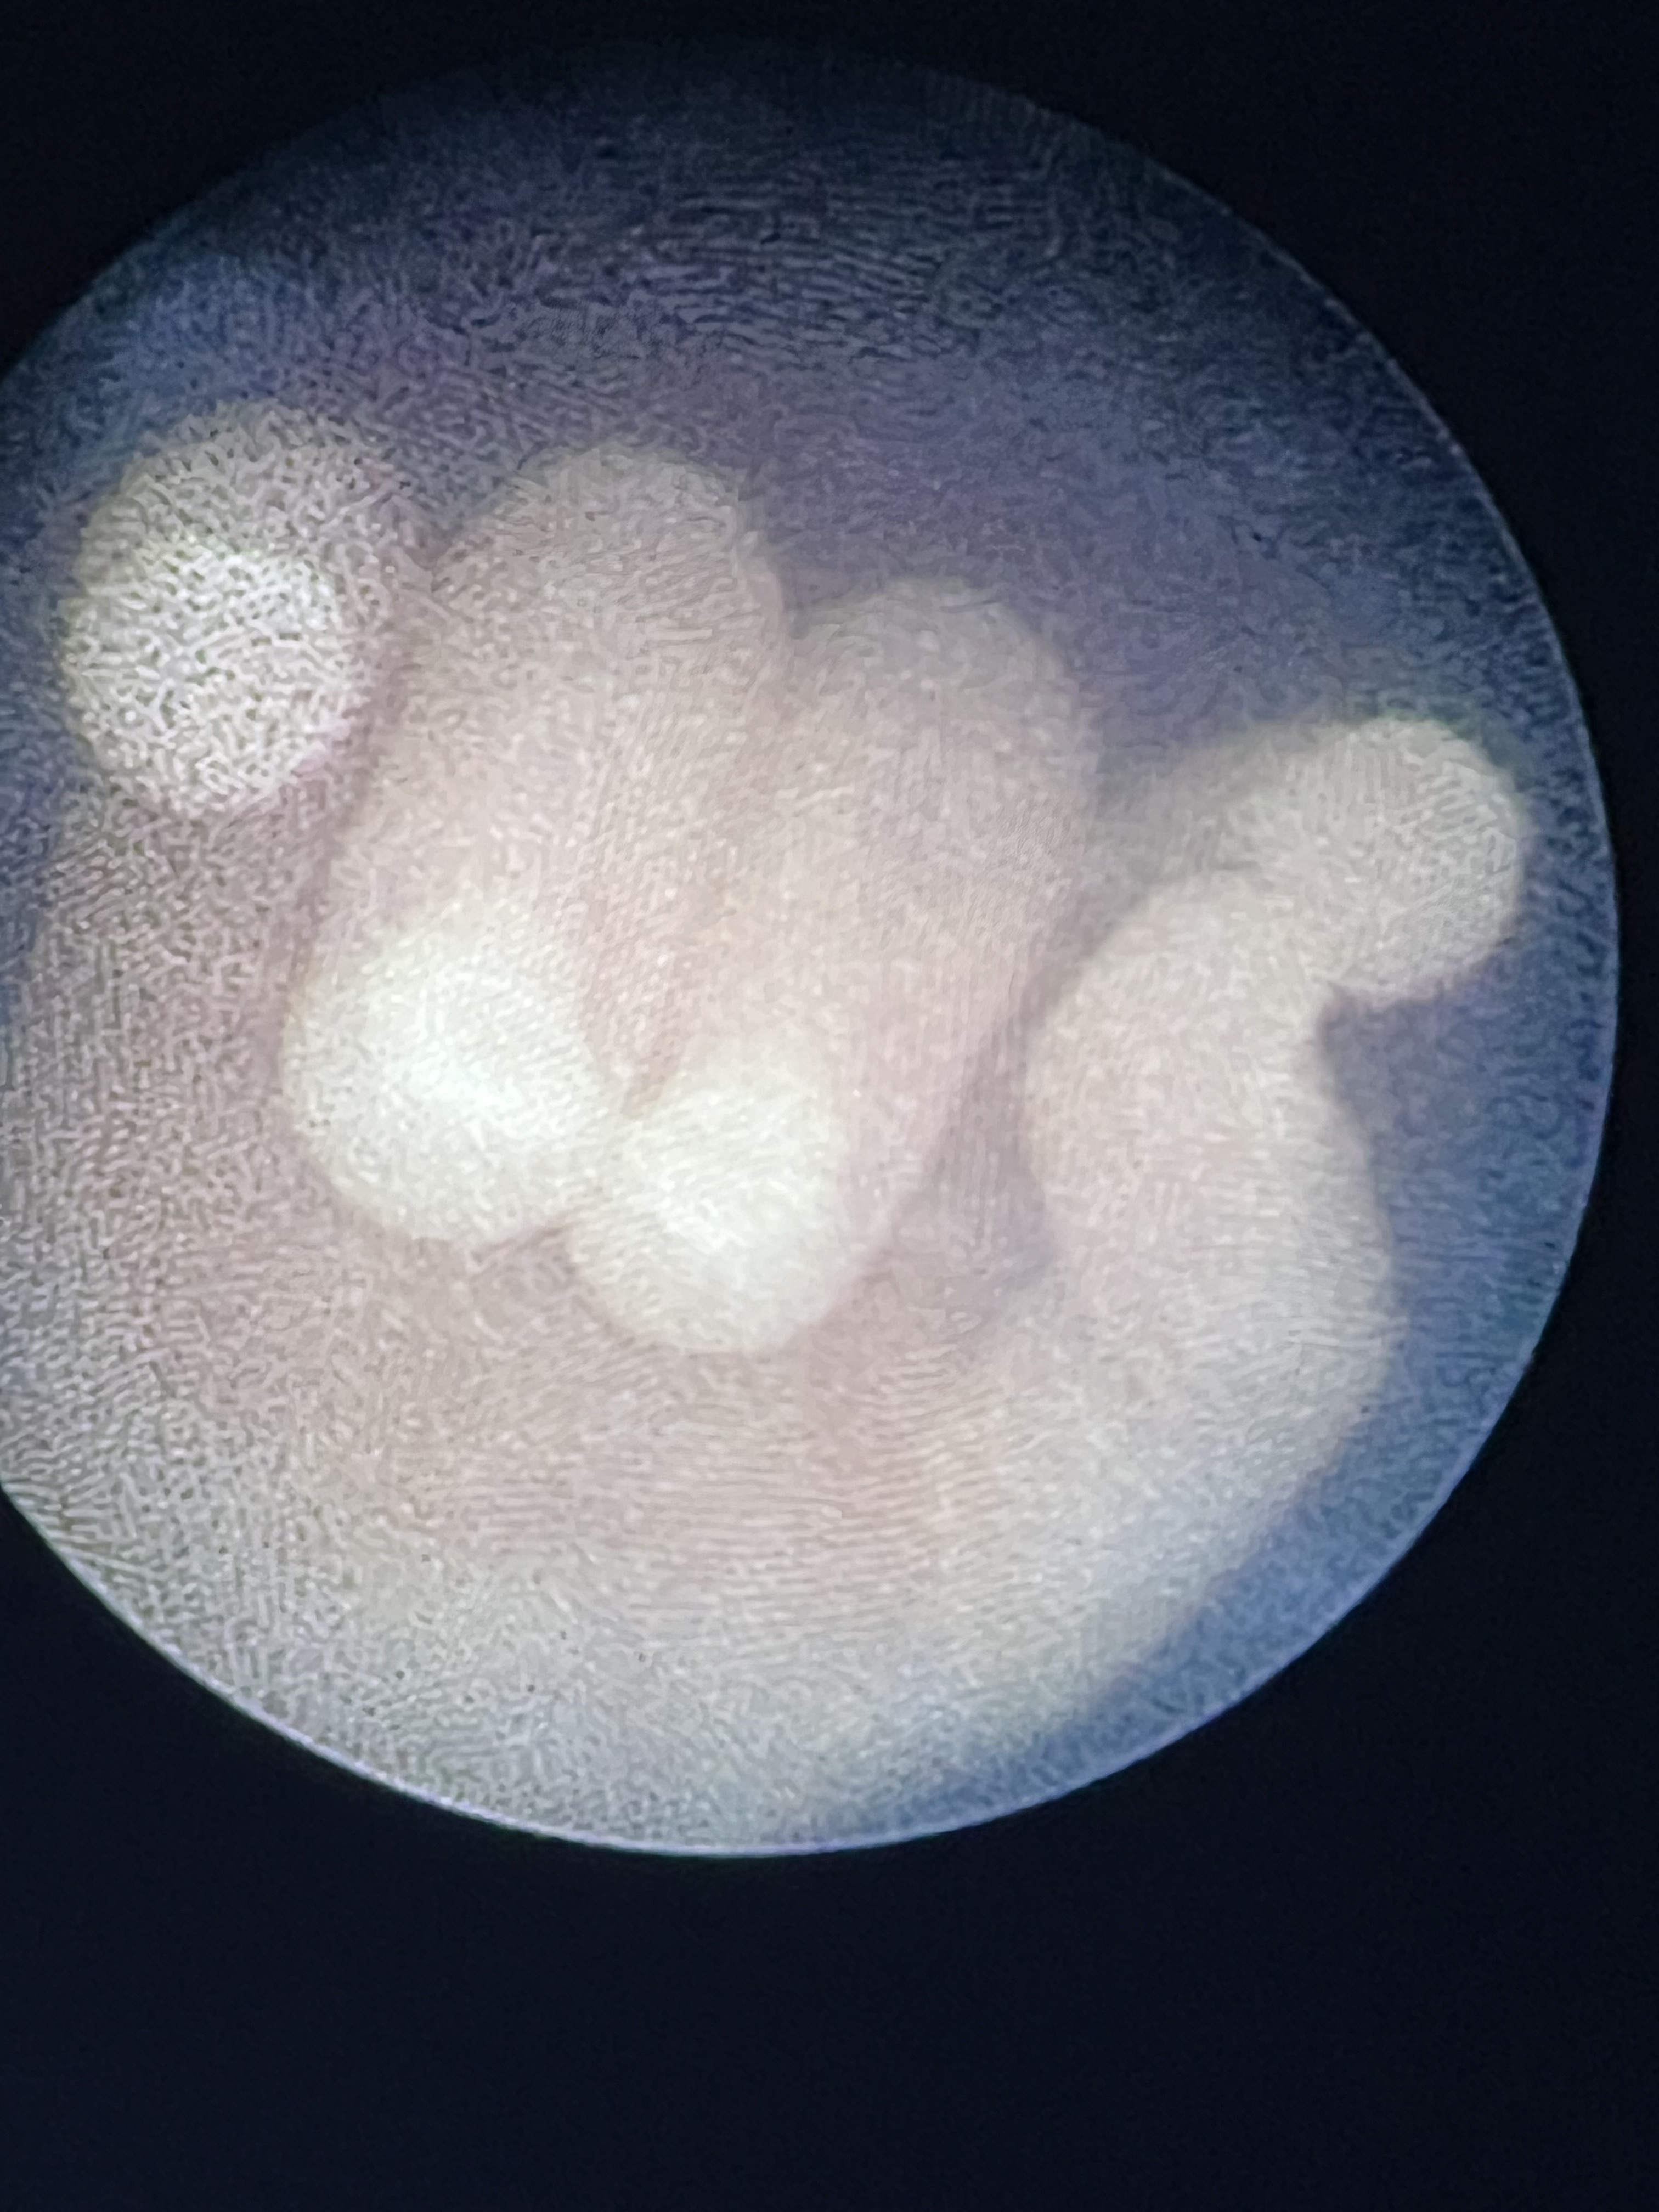

TTTS face

In this first case for the hospital, the mother presented with significant TTTS complications. The recipient fetus was experiencing heart failure and an accumulation of fluid in the abdominal and chest cavities. Banner’s fetal surgery team used a fetoscope inserted into the uterus through a small incision in the mother’s abdomen to close the twin fetus’ abnormal blood vessel connections and restored equal blood flow.